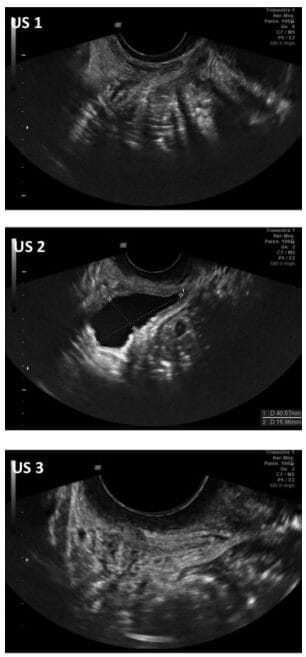

In 2014, a French research team led by Dr. Samuel Salama published the first study to combine two methods at once: pelvic ultrasound and lab analysis of fluids.

Seven women who regularly experienced massive fluid release during arousal took part. Each woman emptied her bladder fully before the session. An ultrasound confirmed the bladder was empty. She then had sexual contact until squirting occurred. Her bladder was scanned again just before and just after the release.

Fluid samples were collected and sent to a lab. Results were clear and the same across all seven women.

What the Ultrasound Showed

Before any arousal, every woman’s bladder was completely empty — confirmed by scan. During arousal, the bladder had filled up significantly. Right after squirting, it was empty again.

This sequence repeated in all seven women without exception. Even after each woman had just urinated, the bladder refilled during arousal and emptied again with squirting.

The source of the fluid was plain: the bladder. No other organ could account for that volume.